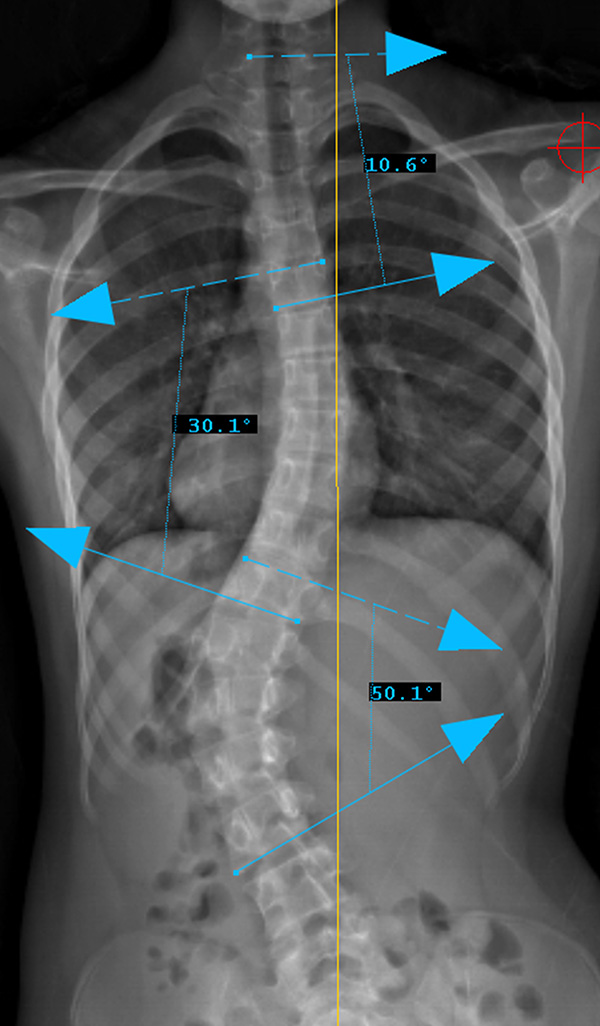

الدراسة وجدت أن سرعة نمو العمود الفقري نفسه ترتبط بتفاقم الانحناء أكثر من زيادة الطول الكلي للجسم.

أظهرت النتائج أن:

الفتيات اللواتي كان لديهن نمو أسرع في العمود الفقري كن أكثر عرضة لزيادة الانحناء بسرعة.

سرعة نمو العمود الفقري كانت مؤشرًا أقوى لتوقع تفاقم الجنف مقارنة بزيادة الطول العام.

بمعنى آخر:

إذا كان العمود الفقري ينمو بسرعة، فهناك احتمال أكبر أن يزداد الانحناء خلال تلك الفترة، حتى لو لم يكن هناك ارتفاع ملحوظ جدًا في الطول الكلي.

سرعة نمو العمود الفقري تُعد مؤشرًا مهمًا جدًا لتوقع تفاقم الجنف عند الفتيات في مرحلة ما قبل البلوغ وأثناءه.

ليست زيادة الطول العام وحدها هي العامل الحاسم، بل نمو العمود الفقري نفسه هو المفتاح الحقيقي لفهم متى قد يزداد الانحناء.